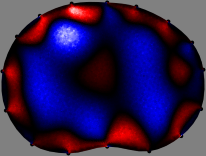

Figs. 3 and 4 compare the performance of the proposed FER method in (20) with the standard regularized least-squares method ((19) when \mathcal{R} is the identity matrix). The regularization parameter of the standard method was heuristically chosen for its best performance, and the parameter of the FER method was set to be one of three different values λ=0.05,0.2,𝜆0.050.2\lambda=0.05,0.2,\infty. The injection current was 1 mARMSRMS{}_{\tiny{\mbox{RMS}}} at 100 kHz, and the frame rate was 9 frames per second. The reference frame at t0subscript𝑡0t_{0} was obtained from the maximum expiration state. The measured data, 𝐕˙(tm)˙𝐕subscript𝑡𝑚\dot{\mathbf{V}}(t_{m}), represent the voltage differences between each time tmsubscript𝑡𝑚t_{m} and t0subscript𝑡0t_{0}. The blue regions, which denote where conductivity decreased by inhaled air, increased during inspiration and decreased during expiration. The FER method with λ=𝜆\lambda=\infty was clearly more robust than the standard method that produced more artifacts originated from the inversion process.

Figure 3: The reconstructed images of the conductivity change of the subject A by the standard regularized least square method and the proposed fidelity-embedded regularization (FER) method for three difference values λ=0.05,0.2,𝜆0.050.2\lambda=0.05,0.2,\infty. Here, the time step is 0.22 seconds (tm+2tm0.22subscript𝑡𝑚2subscript𝑡𝑚0.22t_{m+2}-t_{m}\approx 0.22).